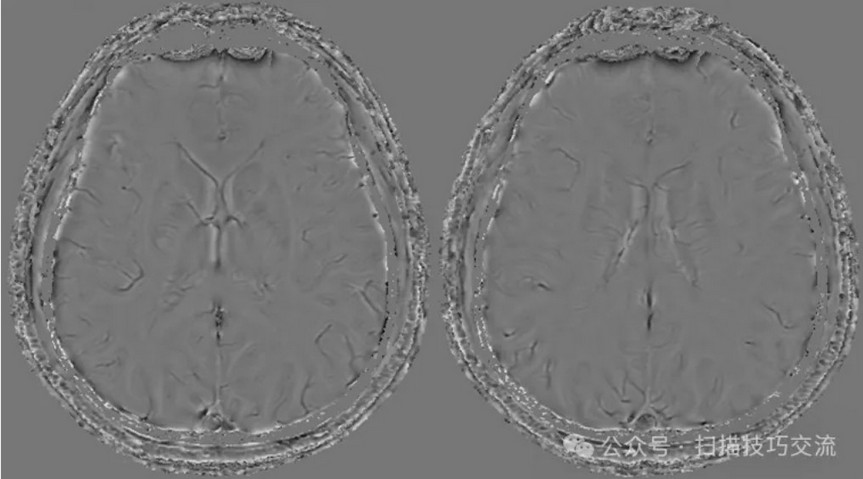

临床申请:颅脑平扫,静脉成像,磁敏感成像,颅内静脉血管黑血成像。

图像不逐一罗列,未见异常。

SWAN未见异常。

PC-MRV未见异常。

颅内静脉黑血成像,CUBE T1fs w/o +c,静脉窦未见异常。